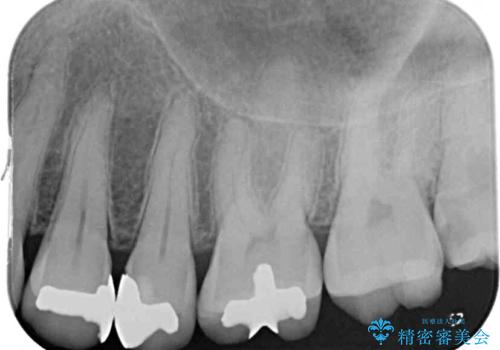

- 銀歯をセラミックにしたいとのことで来院された患者様です。

まず麻酔をして銀歯を外し、むし歯を除去し、形を整えて型取りします。